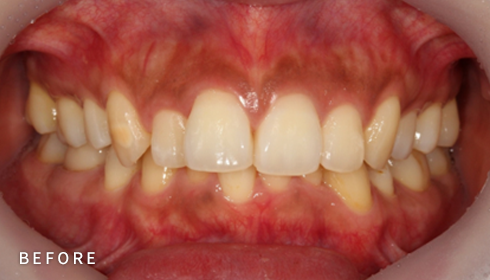

설측교정은 치아 안쪽(설측면)에 초소형 장치로 보이지 않게

아름다운 미소를 만드는 고난이도 프리미엄 교정 치료입니다.

난이도가 높은 만큼 풍부한 진료 경험이 중요합니다.

강남에서 다년간 설측교정에 특화된 경험을 바탕으로,

3D 디지털 기술을 활용한 맞춤 설계, IDBS방식을 통한

정밀하고 불편감 없는 치료를 제공합니다.